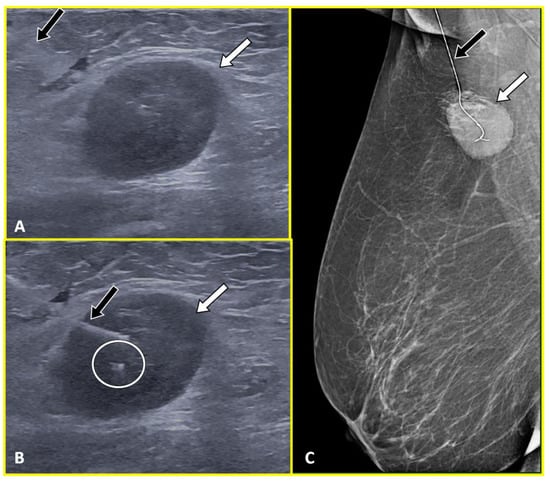

2.1. Marker Clips and Intraoperative Ultrasonography

- Siso, C.; de Torres, J.; Esgueva-Colmenarejo, A.; Espinosa-Bravo, M.; Rus, N.; Cordoba, O.; Rodriguez, R.; Peg, V.; Rubio, I.T. Intraoperative Ultrasound-Guided Excision of Axillary Clip in Patients with Node-Positive Breast Cancer Treated with Neoadjuvant Therapy (ILINA Trial): A New Tool to Guide the Excision of the Clipped Node After Neoadjuvant Treatment. Ann. Surg. Oncol. 2018, 25, 784–791. [Google Scholar] [CrossRef]

- Boughey, J.C.; Ballman, K.V.; Le-Petross, H.T.; McCall, L.M.; Mittendorf, E.A.; Ahrendt, G.M.; Wilke, L.G.; Taback, B.; Feliberti, E.C.; Hunt, K.K. Identification and Resection of Clipped Node Decreases the False-Negative Rate of Sentinel Lymph Node Surgery in Patients Presenting With Node-Positive Breast Cancer (T0-T4, N1-N2) Who Receive Neoadjuvant Chemotherapy: Results From ACOSOG Z1071 (Alliance). Ann. Surg. 2016, 263, 802–807. [Google Scholar] [CrossRef] [PubMed]

- Caudle, A.S.; Yang, W.T.; Krishnamurthy, S.; Mittendorf, E.A.; Black, D.M.; Gilcrease, M.Z.; Bedrosian, I.; Hobbs, B.P.; DeSnyder, S.M.; Hwang, R.F.; et al. Improved Axillary Evaluation Following Neoadjuvant Therapy for Patients With Node-Positive Breast Cancer Using Selective Evaluation of Clipped Nodes: Implementation of Targeted Axillary Dissection. J. Clin. Oncol. Off. J. Am. Soc. Clin. Oncol. 2016, 34, 1072–1078. [Google Scholar] [CrossRef] [PubMed]